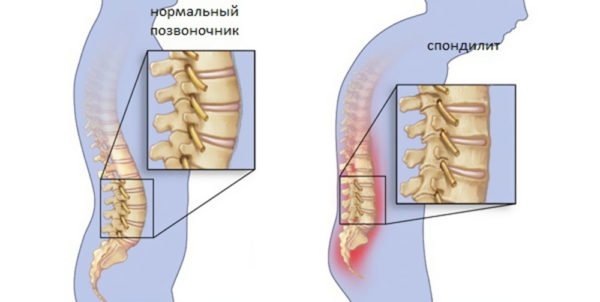

- Воспалительные.

Последний пункт – это рак. К инфекциям относят туберкулез. Воспаление выражается спондилитом.

Спондилит

Патология[править | править код]

Механическое смещение одного из поясничных позвонков, переохлаждение, локальная инфекция, опухоли, деградация тканей, могут привести к воспалительному процессу в позвоночно-двигательном сегменте, последующим мучительным болям, вынужденным положениям тела. Очень распространённой причиной патологии в поясничном отделе позвоночника является неверное распределение нагрузки на поясничный отдел позвоночника, когда дополнительный вес (а иногда и собственный вес) поднимаются с единственным рычагом в поясничном отделе позвоночника. Частым заболеванием в поясничном отделе позвоночника являются грыжи межпозвоночных дисков — выпячивания пульпозного ядра диска за пределы его фиброзного кольца. В 48 % случаев межпозвоночные грыжи локализуются на уровне L5-S1 пояснично-крестцового отдела, в 46 % случаев — на уровне L4-L5, и лишь в оставшихся 6 % случаев — между другими позвонками поясничного, шейного или грудного отделов позвоночника.